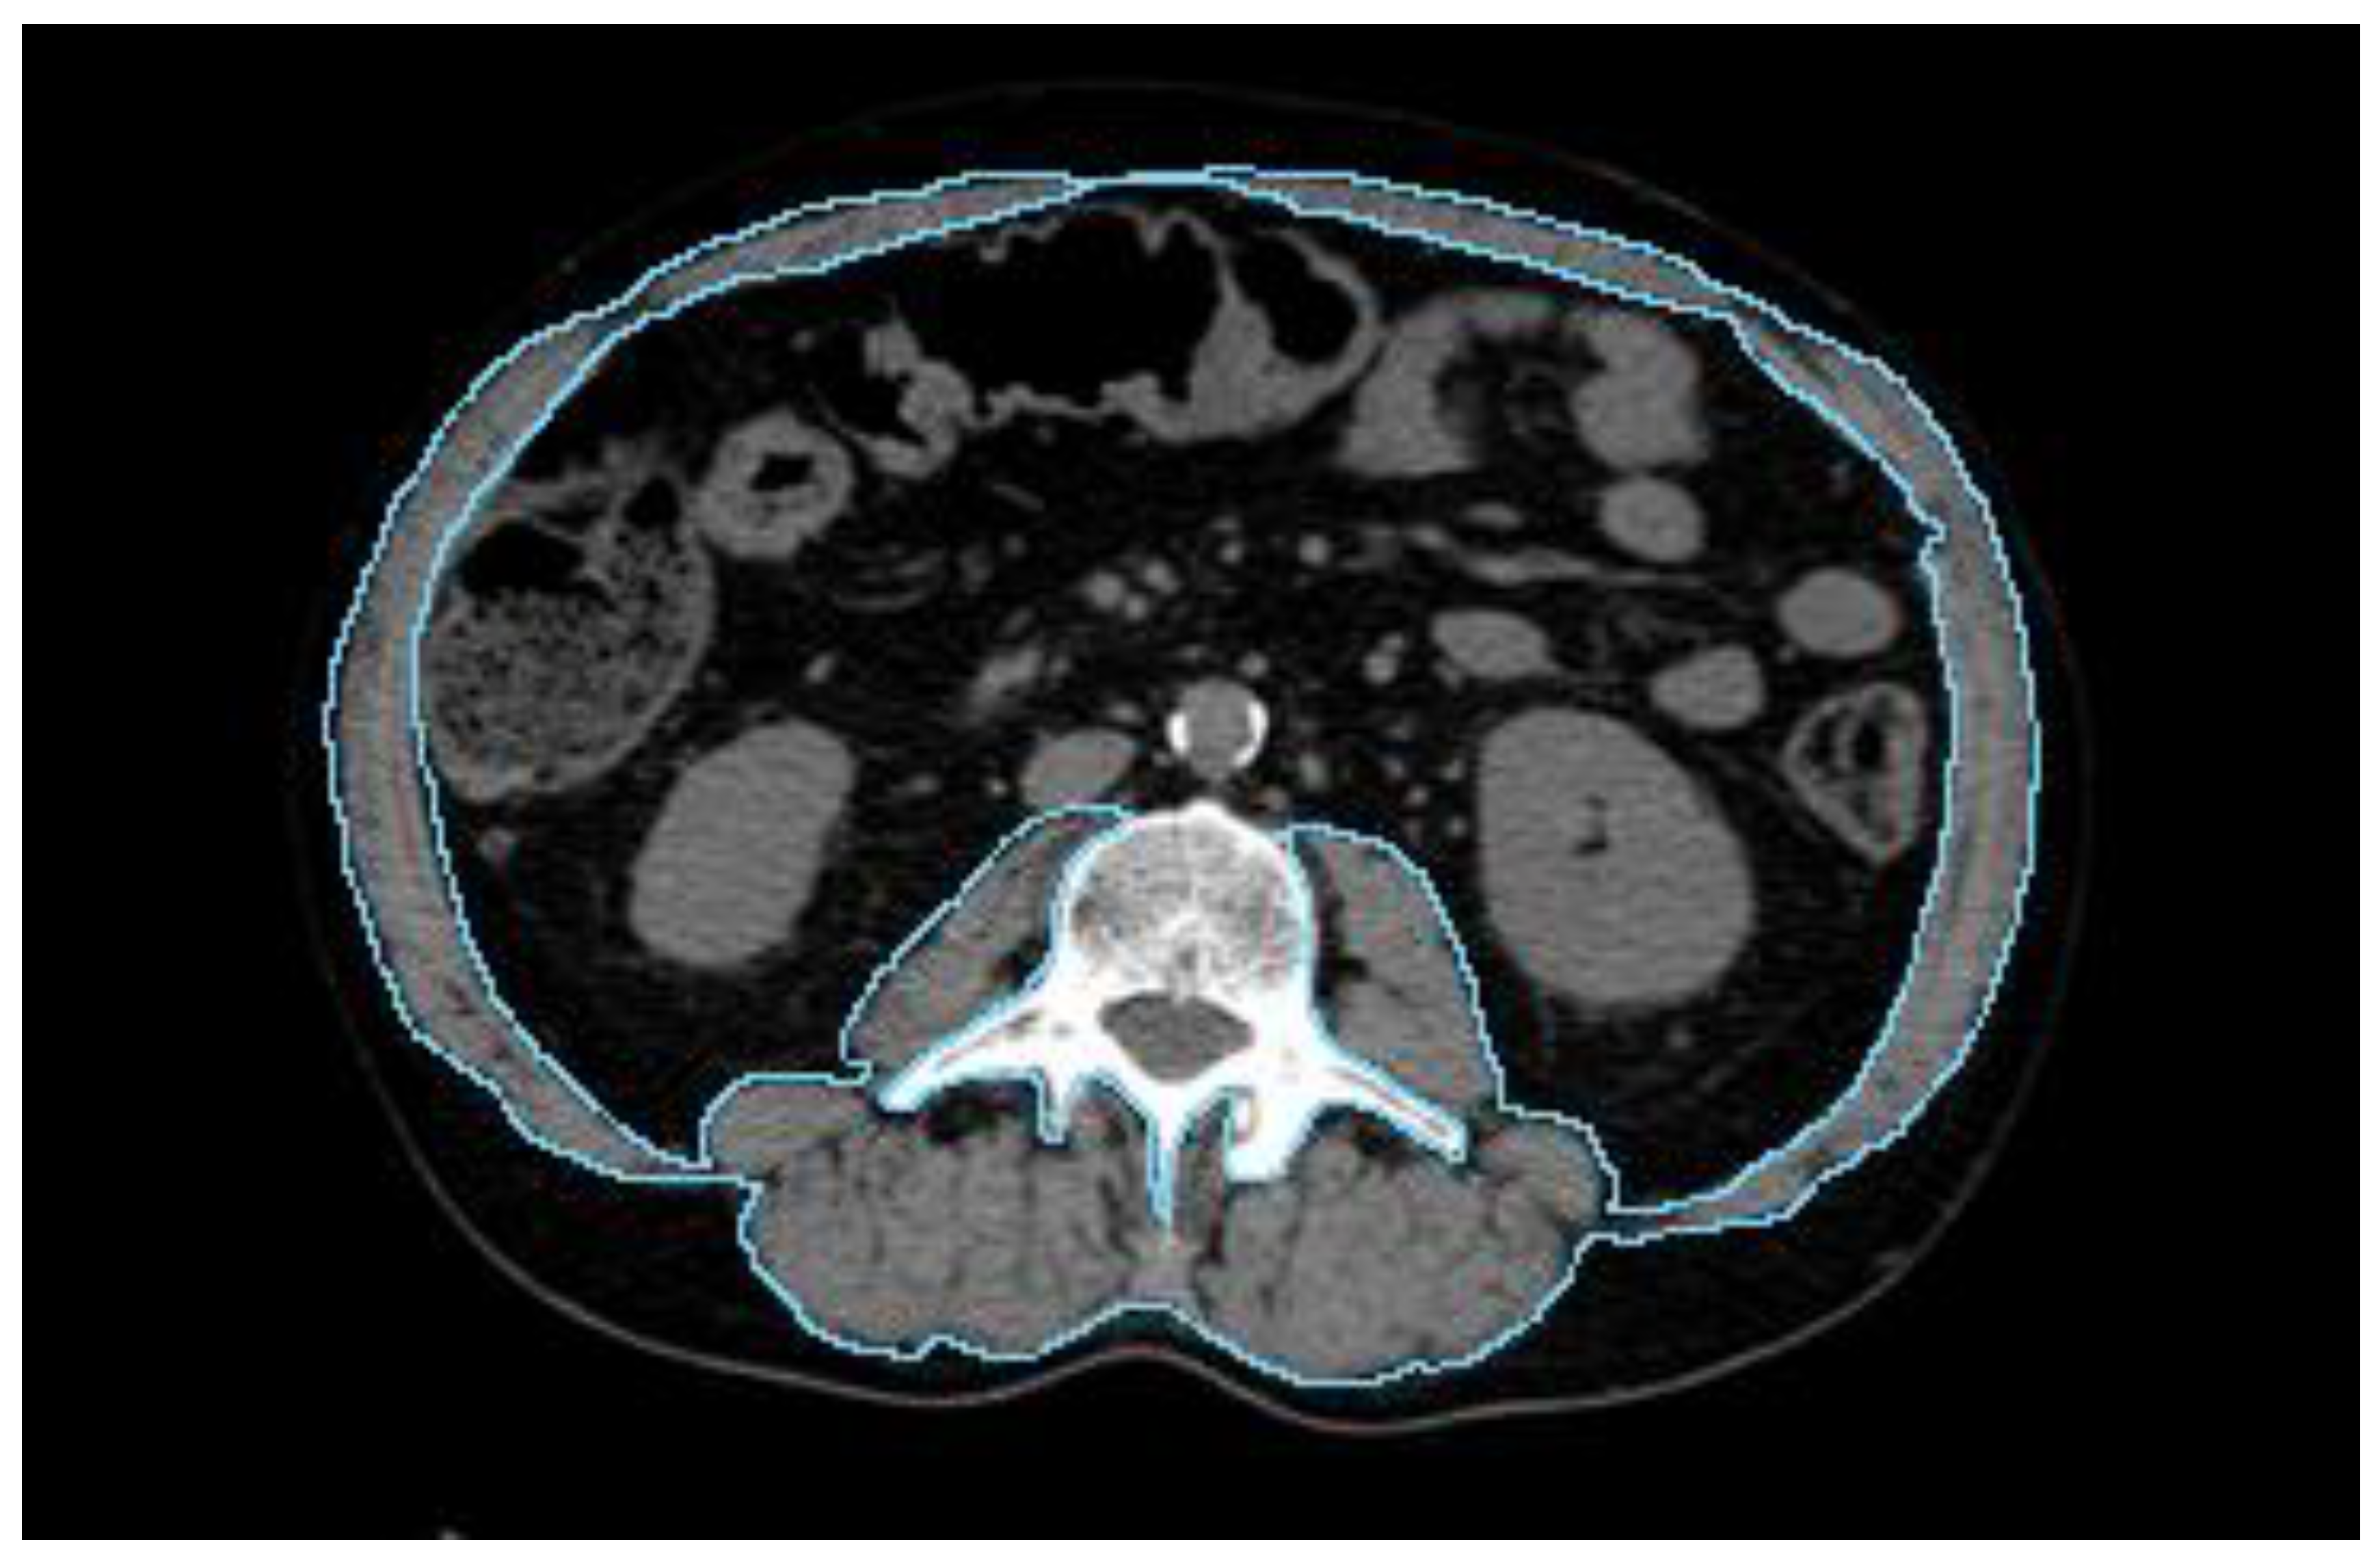

2.3.2. Body Composition Parameters

- Amini, B.; Boyle, S.P.; Boutin, R.D.; Lenchik, L. Approaches to Assessment of Muscle Mass and Myosteatosis on Computed Tomography: A Systematic Review. J. Gerontol. A Biol. Sci. Med. Sci. 2019, 74, 1671–1678. [Google Scholar] [CrossRef]

- Shen, W.; Punyanitya, M.; Wang, Z.; Gallagher, D.; St-Onge, M.-P.; Albu, J.; Heymsfield, S.B.; Heshka, S. Total body skeletal muscle and adipose tissue volumes: Estimation from a single abdominal cross-sectional image. J. Appl. Physiol. 2004, 97, 2333–2338. [Google Scholar] [CrossRef] [PubMed]